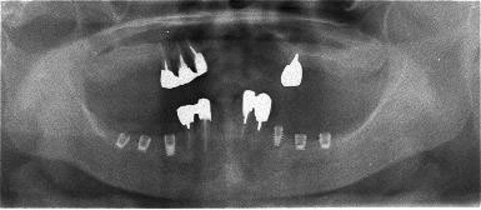

術前レントゲン

術後レントゲン